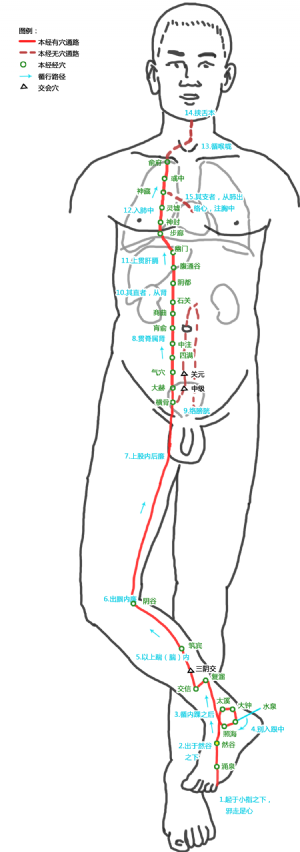

然谷爲經穴名(Rángǔ KI2)[3]。出《黃帝內經靈樞·本輸》。別名龍淵、然骨[4]。屬足少陰腎經[4]。然谷是足少陰腎經的滎穴,五行屬火[4][5]。此穴在舟骨之下,舟骨古稱然骨,故名然谷[5]。然谷穴主治婦科、前陰、脾胃等疾患:如月經不調,陰挺陰癢,痛經,白帶,血崩,不孕,遺精白濁,小便淋瀝,疝氣,黃疸,消渴,泄瀉,頭痛,喉痹,厥心痛,咳喘,咯血,胸滿,腰脊痛,癲疾,臍風,腳氣,腳腿轉筋,瘡疥癬癢,咳血,陰癢,陰挺,陽痿,遺精,臍風口噤,足跗腫痛,帶下,咽喉腫痛,口噤,小便不利,小兒臍風,胸脅脹痛,口噤不開,下肢痿痹,足跗痛,現代又多用然谷穴治療咽喉炎,扁桃體炎,尿道炎,睾丸炎,精液缺乏,糖尿病,陰部瘙癢,心肌炎,破傷風,足部扭挫傷,膀胱炎,遺尿,不孕症,精神病等。

龍淵爲經穴別名[1][2]。出《鍼灸甲乙經》。即然谷穴[2]。《備急千金要方》作龍泉[2]。